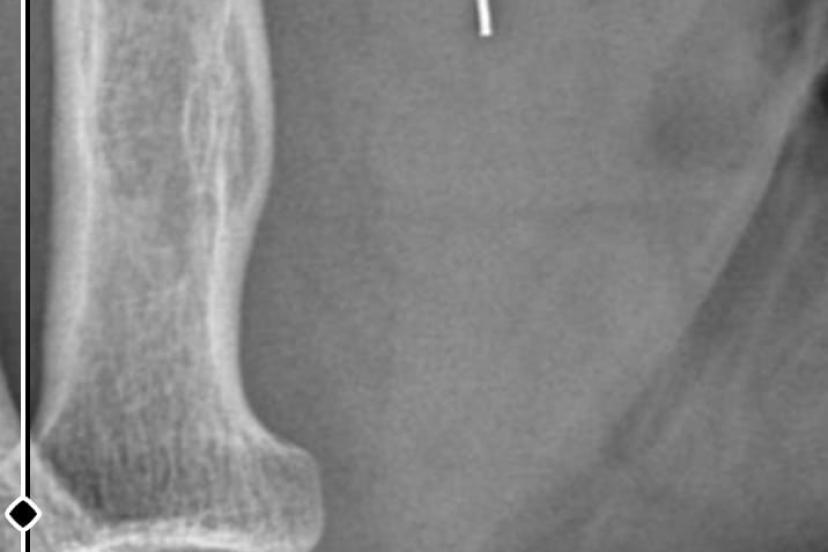

Öte yandan, ameliyatların ardından ağrıları devam eden Güleryüz’ün kolunda metal parça bulunduğu ve bu parçanın parmak bölgesinden dirseğe doğru ilerlediği öne sürüldü. Ayrıca, fabrikada temizlik personeli olarak çalışan Nurettin Güleryüz’ün hastane sürecinde işten çıkarıldığı da öğrenildi.

"Doktorlara bileğime doğru ağrılarım olduğunu sürekli ifade etmeme rağmen beni dinlemediler. Sonradan kolumda metal kaldığını öğrendik. Bunun ihmal olduğunu düşünüyoruz. Çünkü kola metal nasıl girebilir? Ben 9 aydır çalışamıyorum. Kalp rahatsızlığım sebebiyle yüzde 46 engelliyken şu anda yüzde 75 engelli durumuna düştüm. Erken emeklilik dilekçesi verdim ancak henüz sonuç gelmedi. Bu konuda çok mağdurum. Yetkililerin bunu duymasını istiyorum. Savcılığa suç duyurusunda bulunduk. Yaklaşık 9 aydır henüz soruşturma izni gelmedi. Süreci bekliyoruz, henüz dava açılmış değil. Kolumda bırakılan metal ilerliyor. Pazartesi günü bunun için de operasyon geçireceğim. Çıkarılıp çıkarılamayacağı net değil. Elimde titremelerim var, çalışamıyorum ve işveren tarafından işten çıkarıldım. Yetkililerden destek ve konunun incelenmesini talep ediyorum."